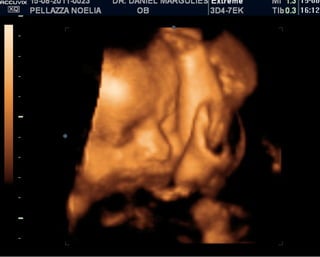

ISABELLA!

ISABELLA! Está viniendo!